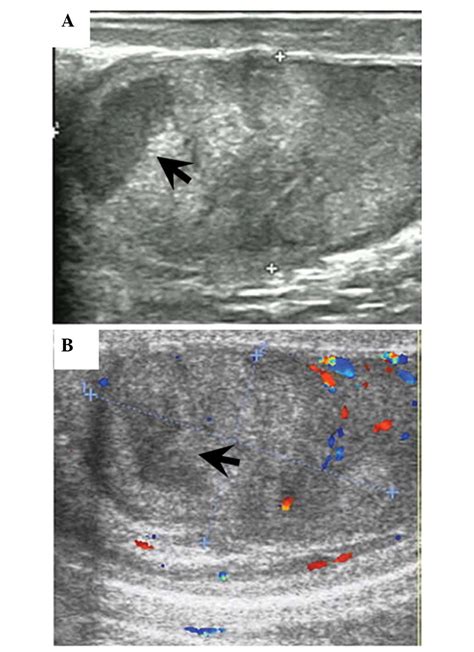

• Ultrasound: This is the most common diagnostic tool for testicular pain. A scrotal ultrasound uses sound waves to create images of the testicle, allowing the doctor to see blood flow, identify fluid buildup, or detect tumors.

These tests are essential because they provide objective data that a physical examination alone cannot yield. For example, an ultrasound can definitively distinguish between the reduced blood flow seen in torsion and the increased blood flow typically associated with inflammation.